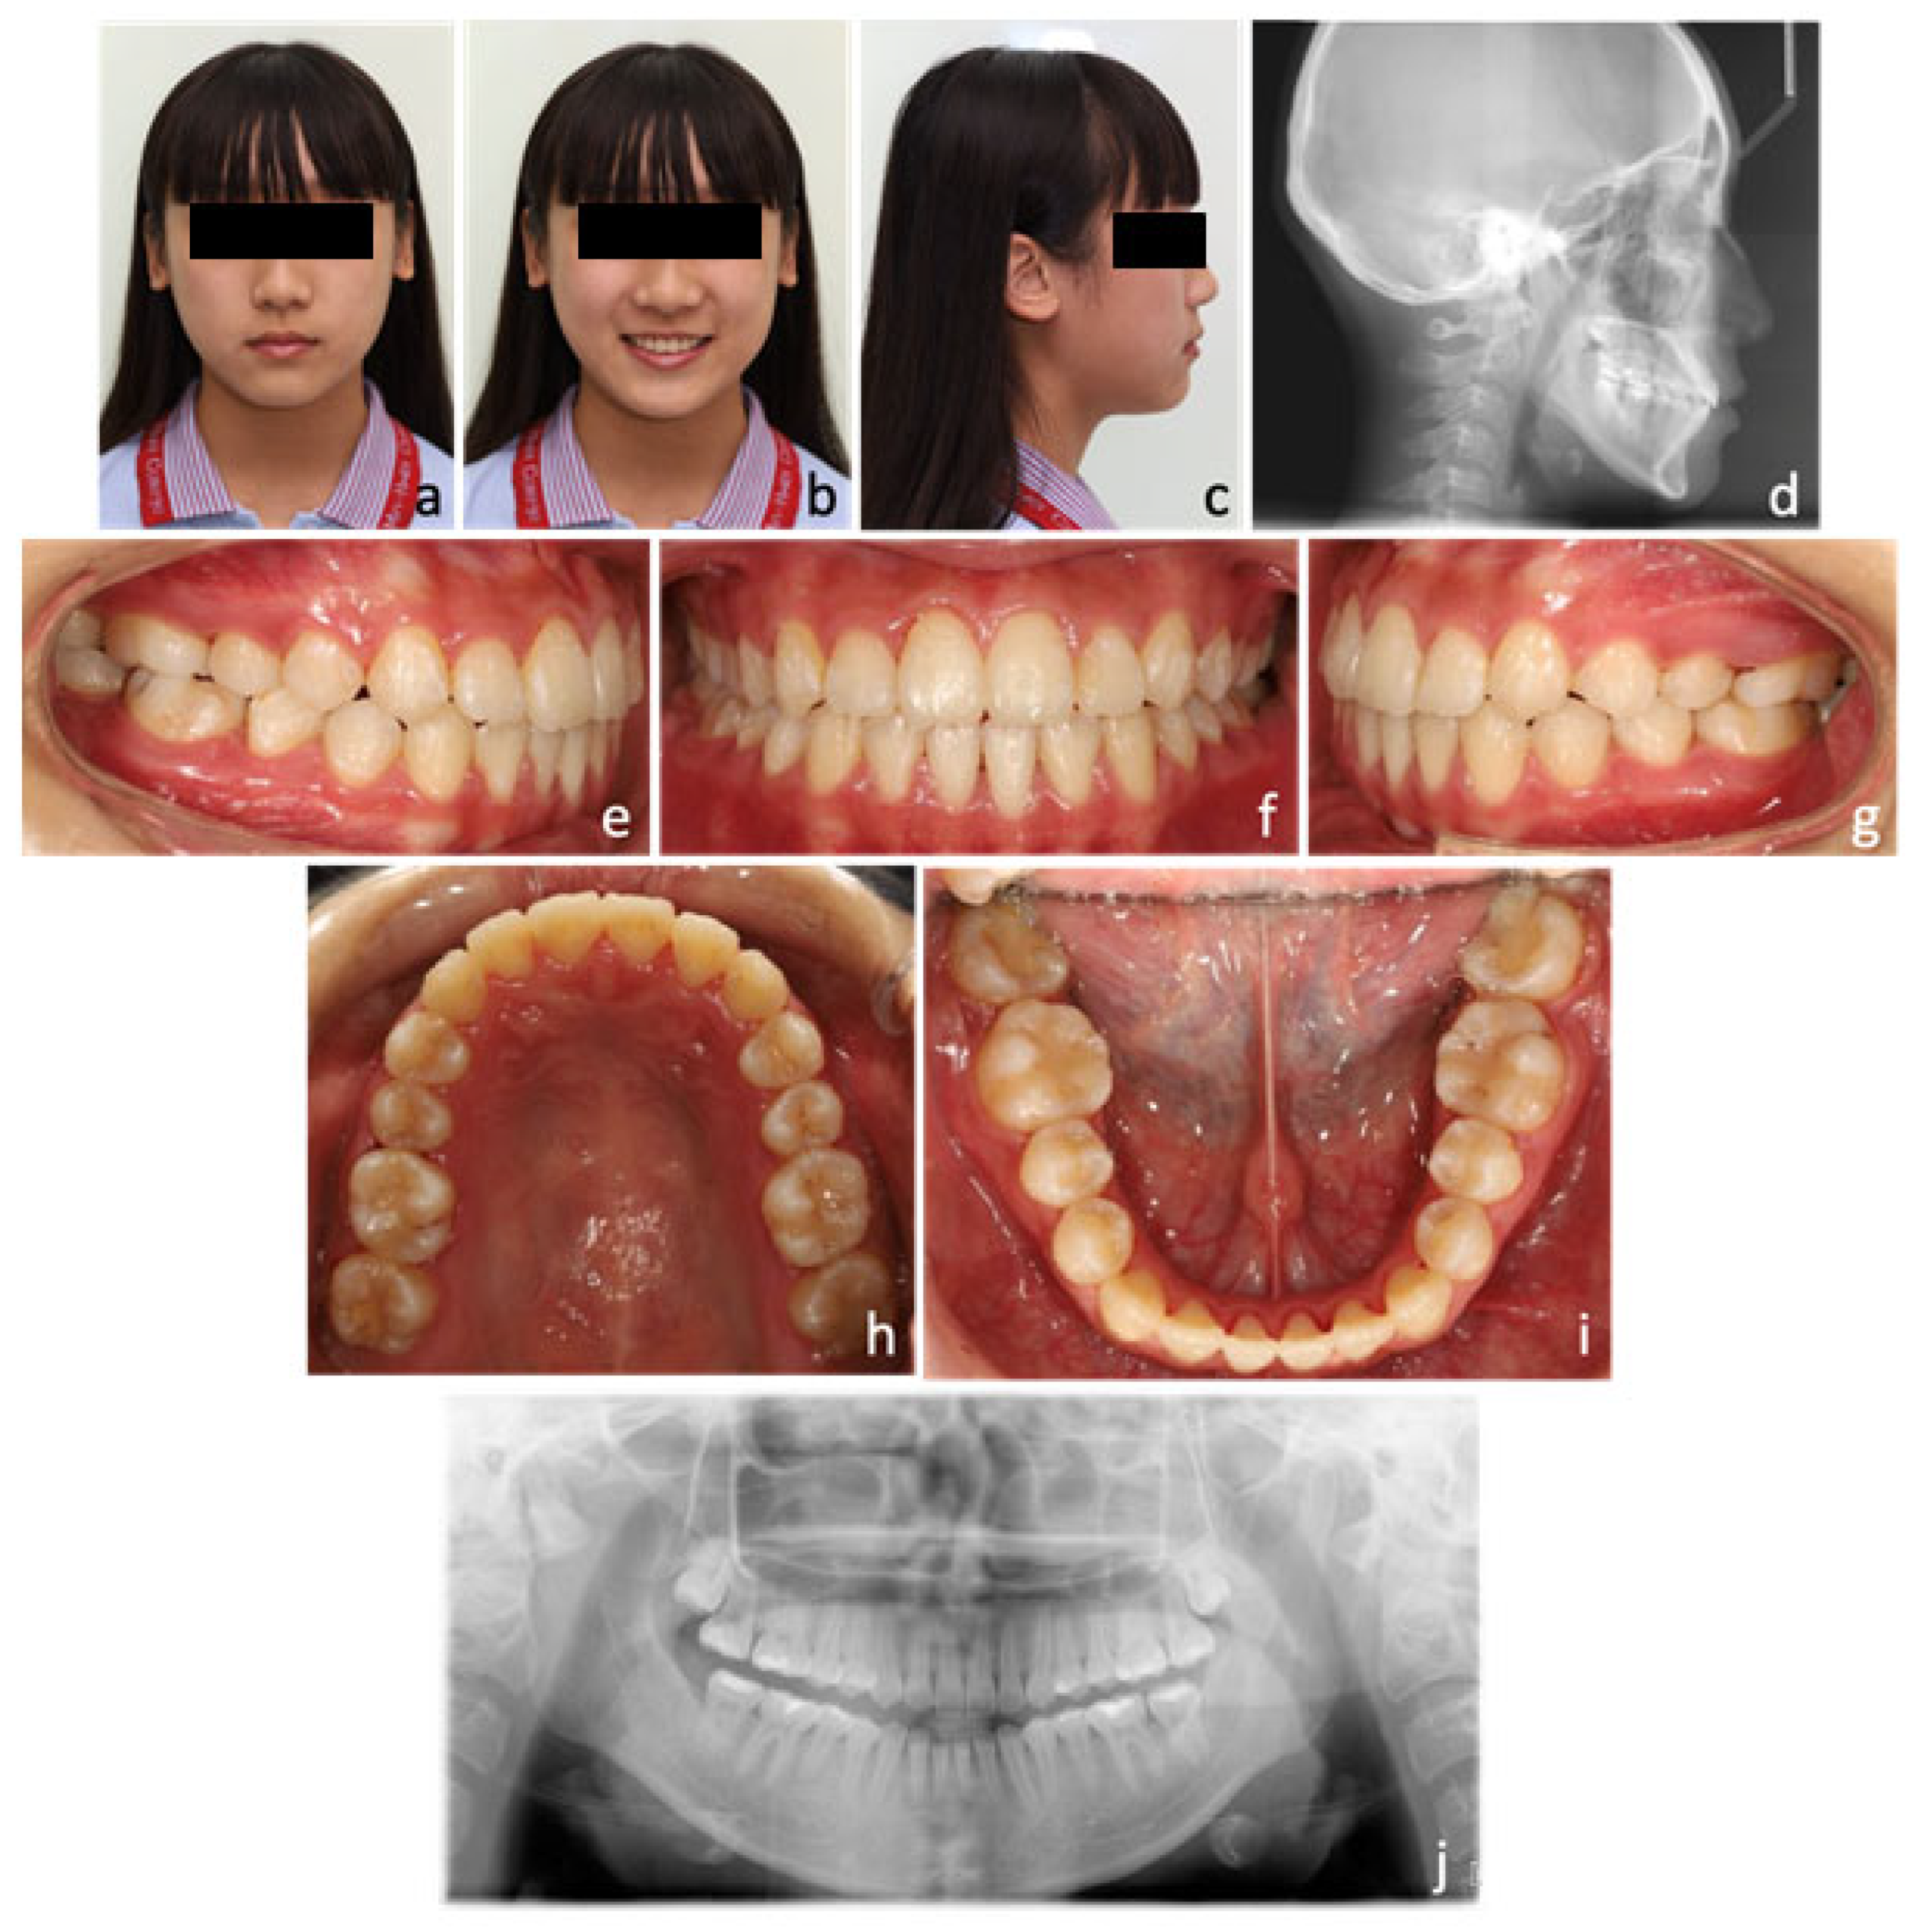

2. Case Report

2.1. Diagnosis and Aetiology